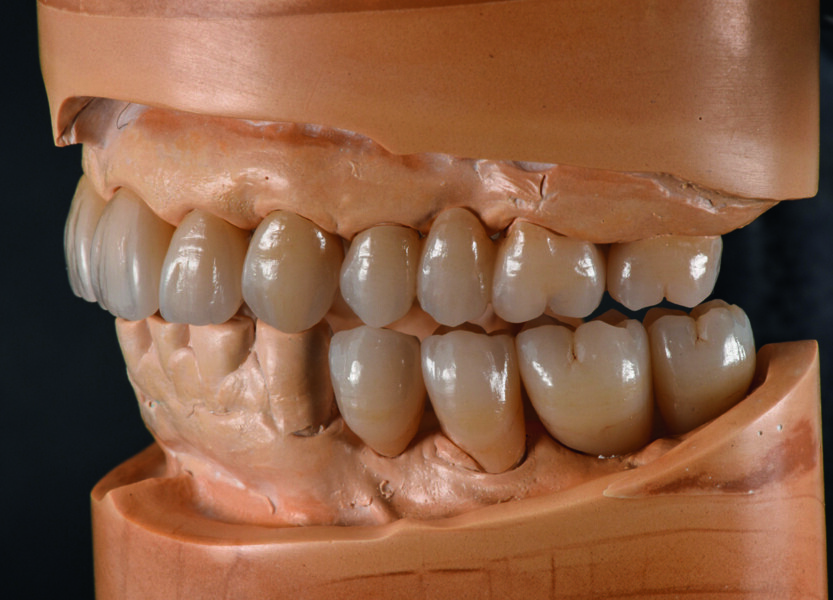

Fig. 9a : Surfaces occlusales et pente canine parfaites pendant le mouvement mandibulaire.

Fig. 9b : Surfaces occlusales et pente canine parfaites pendant le mouvement mandibulaire.

Enfin, je cherche à obtenir une pente canine sans contacts perturbants lors des mouvements de latérotrusion et de protrusion. Ces mouvements sont reproduits adéquatement et exactement, comme je les ai conçus dans l’articulateur Artex CR virtuel (Figs. 9a et b). Le flux de travail méthodique entre l’articulateur manuel et l’articulateur virtuel est tout simplement ingénieux, et simplifie mon travail quotidien. Néanmoins, cela ne fonctionne vraiment bien que si le fabricant coordonne l’articulateur et le système CAD/CAM, ce qui est le cas pour ces produits.